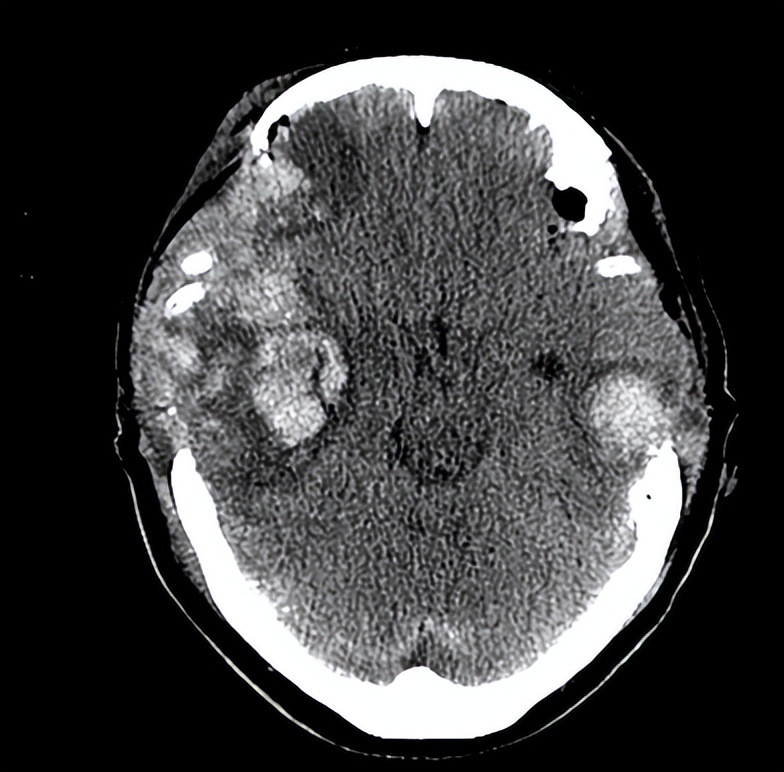

06-07日入院时头CT

重型颅脑外伤,右颞叶脑挫伤,双侧硬膜外、下血肿,蛛网膜下出血,小脑幕裂孔疝,脑干水肿,左额颞顶头皮血肿,左颞顶骨、右蝶骨翼骨折;并于15:00急诊于手术室在全麻下行“左侧硬膜外血肿清除+双侧额颞顶部硬膜下血肿清除+双侧硬脑膜成形+双侧去标准外伤大骨瓣减压术+右侧颞叶挫伤血肿清除颅内减压术+左颞枕部头皮挫裂伤清创缝合术”后(18:10)继续ICU监护治疗。